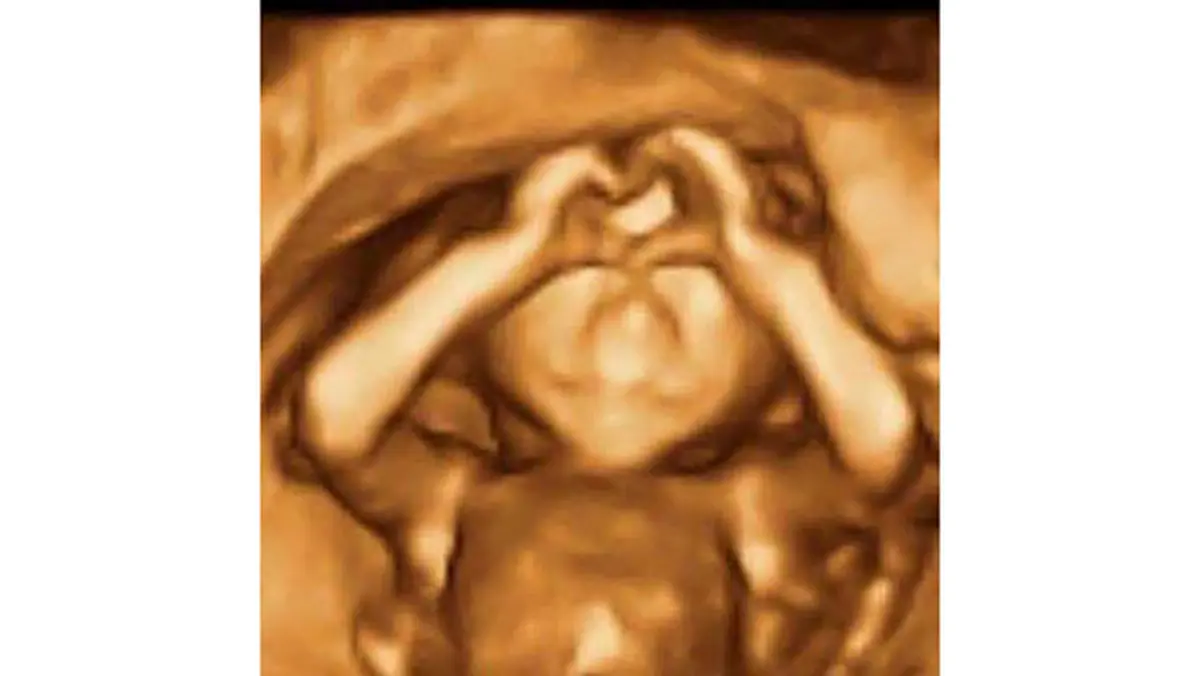

رکنا: تصویر سونوگرافی یک جنین که انگشتان خود را به حالت خاصی در آورده به تازگی در رسانهها و فضای مجازی به سوژه داغ خبری بدل شده است.

در پی انجام یک سونوگرافی سه بعدی از جنین، پزشکان با تصویر شگفت آوری مواجه شدند.

در این سونوگرافی، جنین به طرز شگفت آوری علامت لایک (Like) یا عشق و محبت را با دستان خود نشان می دهد.

امروزه برای تهیه تصاویر سونوگرافی سه بعدی و چهاربعدی از تکنولوژی جدید پزشکی استفاده میشود که طی آن تصاویر دقیقتری از صورت، دست و پای نوزاد به ثبت میرسد.برای ورود به کانال تلگرام ما کلیک کنید.